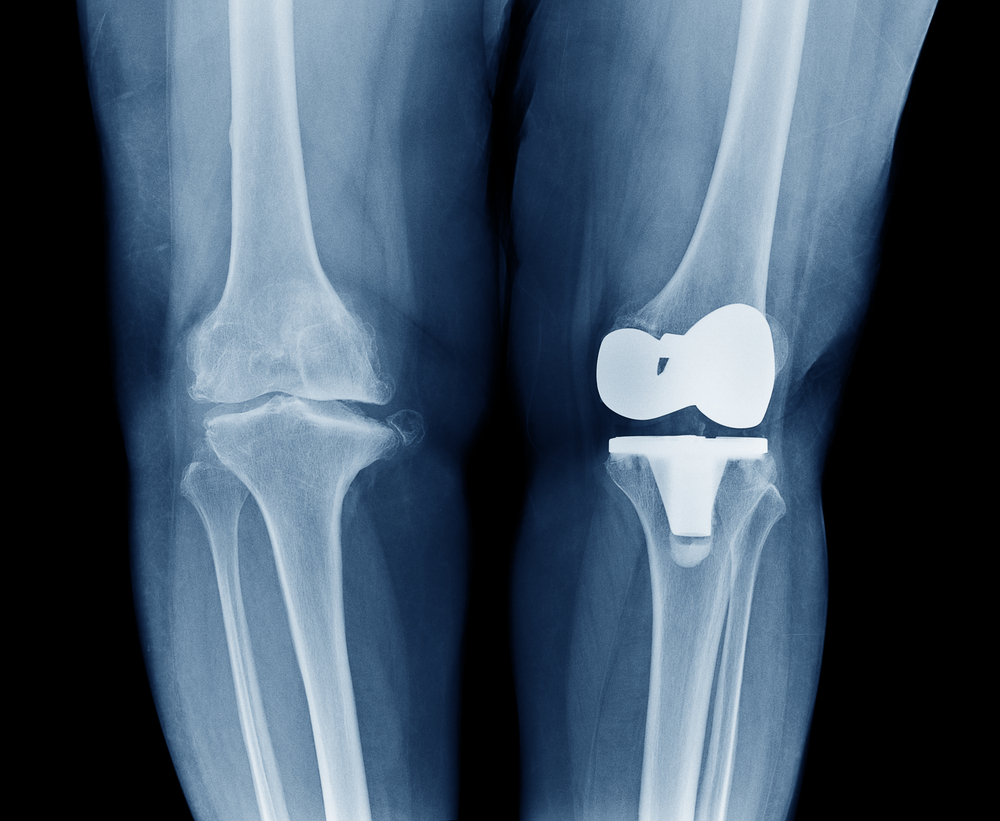

Total knee replacement

The idea of totally replacing your knee might feel overwhelming, but the results of the procedure can be lifechanging. In fact, according to the American Association of Hip and Knee Surgeons, hip and knee replacement surgeries are considered among the most successful treatments in the history of modern medicine.

Guided by a CT scan of your knee, your surgeon will customize a surgical plan specifically for you. During your surgery, the Mako robotic arm provides your doctor with real-time data, including joint movement and tension assessments, which allow him or her to adjust your surgical plan if necessary. Your surgeon uses Mako’s robotic arm to remove arthritic bone and tissue from the knee, replacing it with a safe and pain-free implant.

Partial knee replacement

Sometimes, arthritic damage is caught early enough to avoid replacing the entire knee. If you are in earlier stages of arthritis but suffer from pain, swelling and limited mobility, a partial knee replacement may be a safe and effective treatment option for you.

According to Stryker, manufacturer and seller of the Mako equipment, a partial knee replacement is optimal when arthritis or another inflammatory disease hasn’t progressed to all three compartments of the knee, allowing the surgeon to replace fewer parts of the knee.

Depending on your unique surgical plan, your surgeon may replace one or two areas of the knee. For example, you may require a kneecap (or patella) replacement only or the knee cap along with the inside compartment or the grove of the knee.